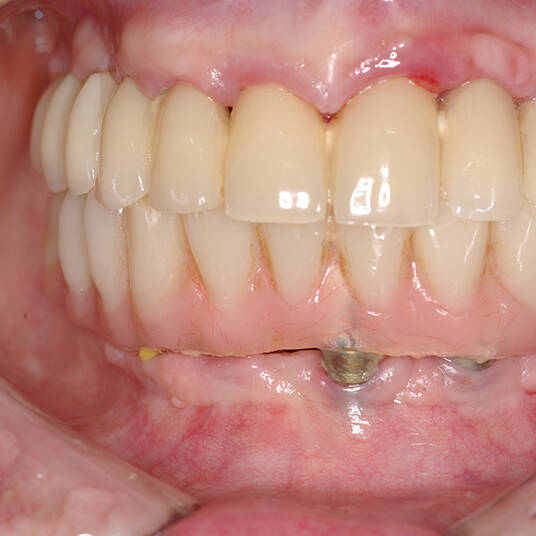

A Carga Imediata é uma técnica odontológica avançada que permite a colocação de uma prótese dentária fixa logo após a cirurgia de instalação dos implantes ou em poucos dias. Isso elimina a espera tradicional de meses para a integração completa do implante ao osso, oferecendo uma solução rápida e segura para restaurar dentes perdidos.

- Fixação da Prótese: Em até 72 horas após a cirurgia, a prótese provisória é instalada, permitindo que o paciente recupere a funcionalidade e a estética imediatamente.

- Conforto e Estética: A prótese provisória é funcional e visualmente semelhante aos dentes naturais.